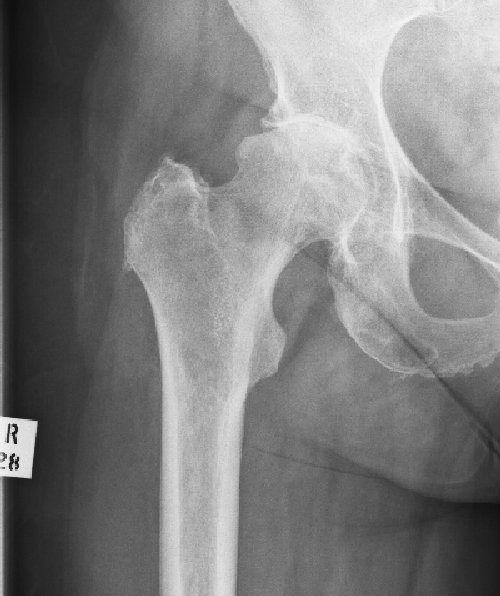

Avascular Necrosis

This is a condition caused by a failure of the blood supply to a part, or the whole, of the femoral head. As the bone is exposed to daily trauma it cannot regenerate and may start to collapse. The extent of the collapse is variable, healing will solidify the head but may lead to a mis-shapen head and therefore early osteoarthritis.

In extreme cases the whole femoral head may fragment and the bone dissolves away.

27/05/2011 - Not operated upon!